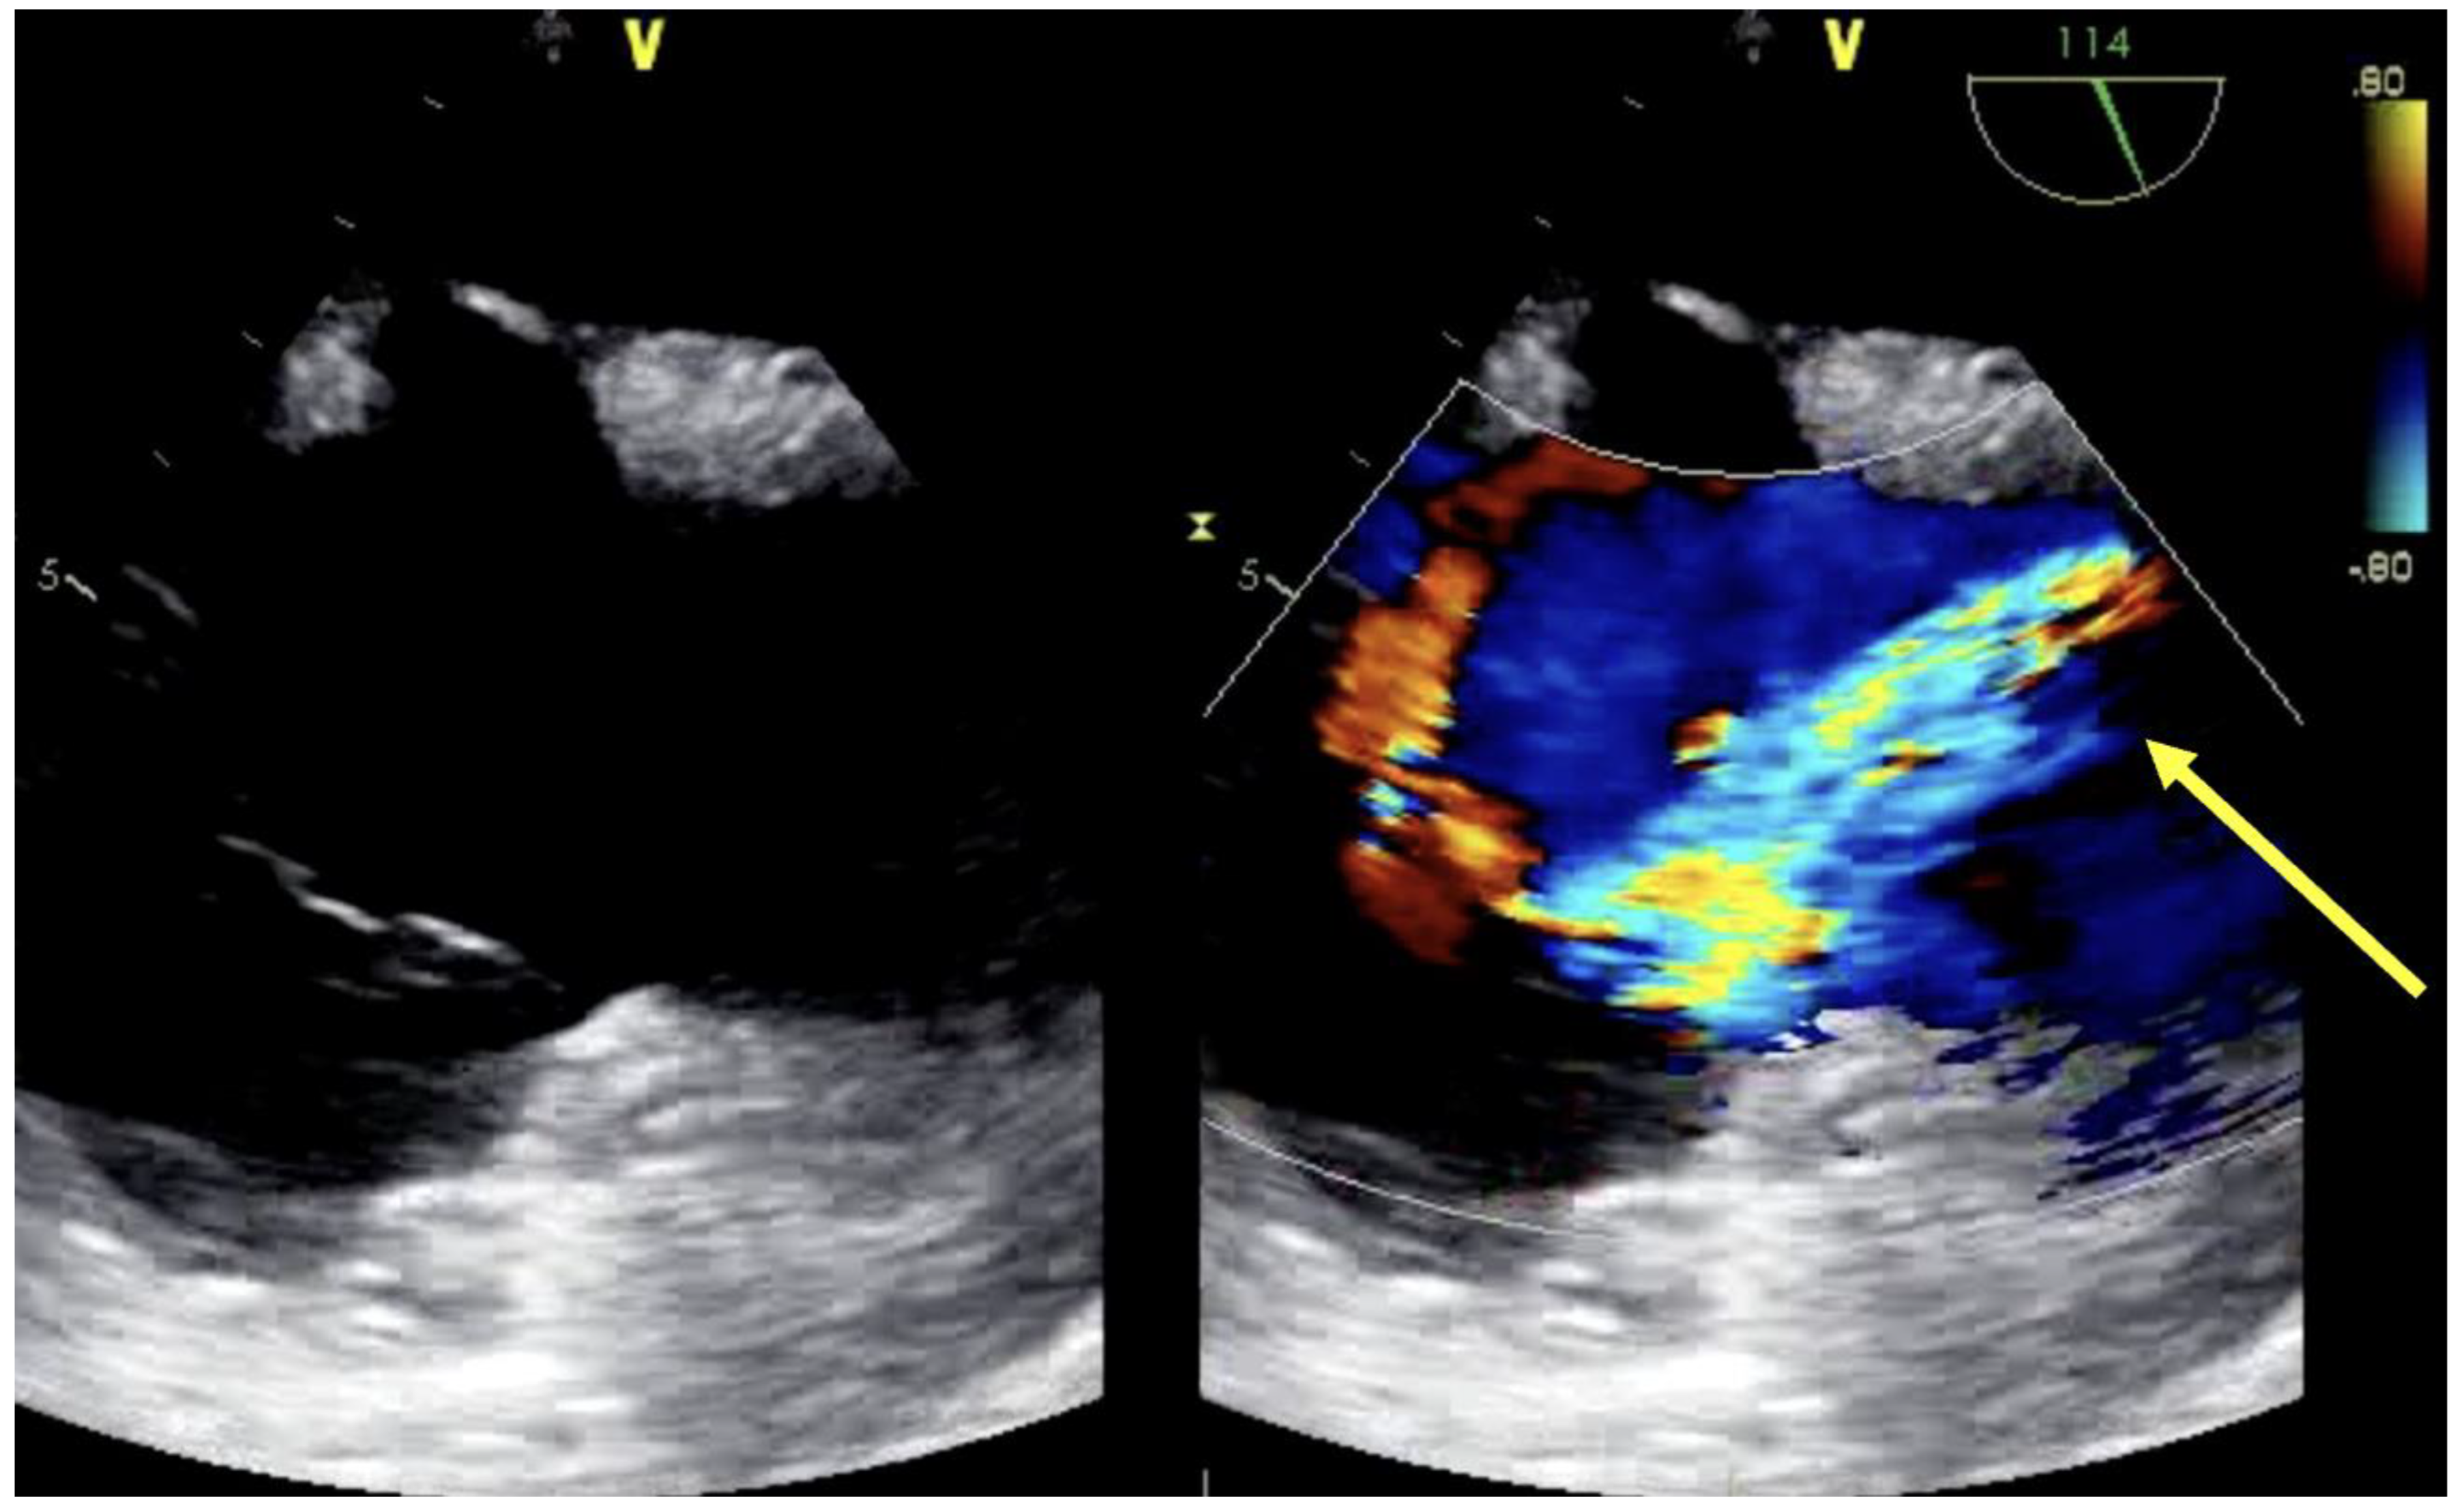

3.2. Dual-Lumen Considerations

| Assessment of peripheral vasculature for size, disease, thrombus | Assessment of return (outflow) “jet” | Confirmation of cannula position |